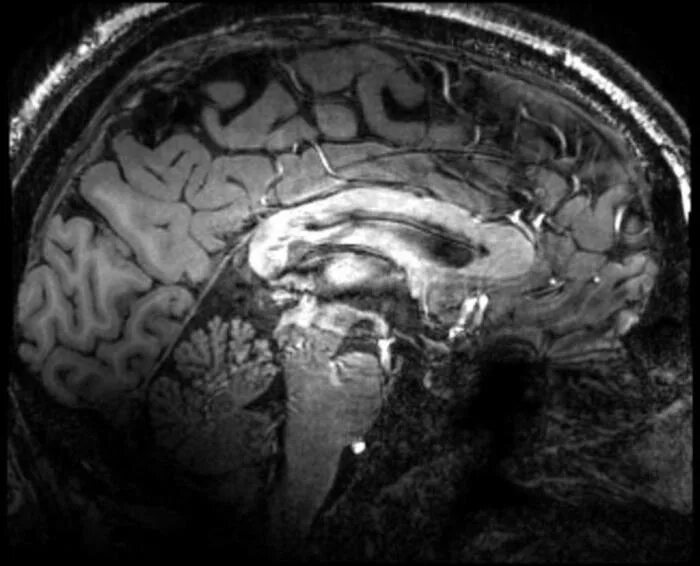

Атеросклероз головного мозга лечение у женщин